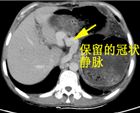

术后1月CT

血栓陈旧无法完全溶解,但因选择性贲周血管离断术保留了冠状静脉,门静脉血流可以通过食管下端交通支返流,无腹水等并发症发生。